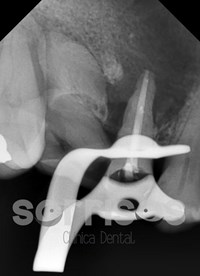

A continuación, un caso de infección recurrente por culpa de la raíz de la pieza 15, que es restaurable, aunque con pronóstico reservado, y la raíz del 16 que no es restaurable. En la radiografía periapical previa, la lesión es tan grande que no se aprecian sus límites. En la radiografía panorámica se observa un tamaño de unos 2 cm de diámetro con desplazamiento de la cortical del seno maxilar.

Radiografía periapical final tras la endodoncia